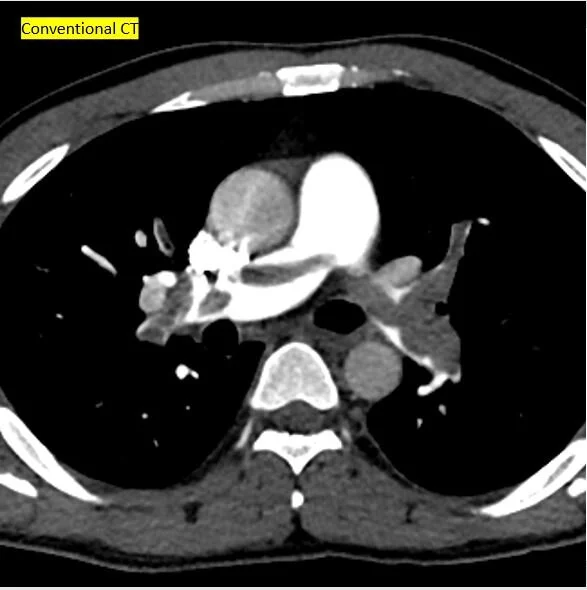

Conventional CT shows large left hemothorax